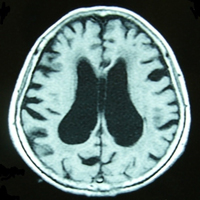

正常圧水頭症外来

当科では正常圧水頭症の治療にも力を入れています。正常圧水頭症は、頭の中の水(髄液)の流れが悪くなることによって起こります。流れが悪くなると、歩行障害(歩くのが遅く、歩幅が小刻みになり、すり足のような歩き方になる)、認知機能障害(物忘れや自発性の低下)、排尿障害(尿漏れ)などがおこります。検査を行い、正常圧水頭症と診断されれば、たまってしまった髄液を他の場所へ逃がし体の中に循環させる治療(髄液シャント術)を行い、症状を軽快させます。

当科では正常圧水頭症の手術を100例以上経験した医師が術後のリハビリテーションも含め、検査・治療にあたります。

(V-Pシャント)

脳内の髄液をお腹に流す

(L-Pシャント)

背骨の中にある髄液をお腹に流す